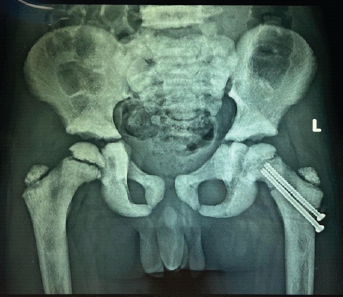

A Rare Case of Left Femoral Neck Fracture in a 6-Year-Old Boy with Osteopetrosis

Sri Harsha Reddy , J K Giriraj Harshavardhan , Sundar Suriyakumar , M Mohammed Tavfiq